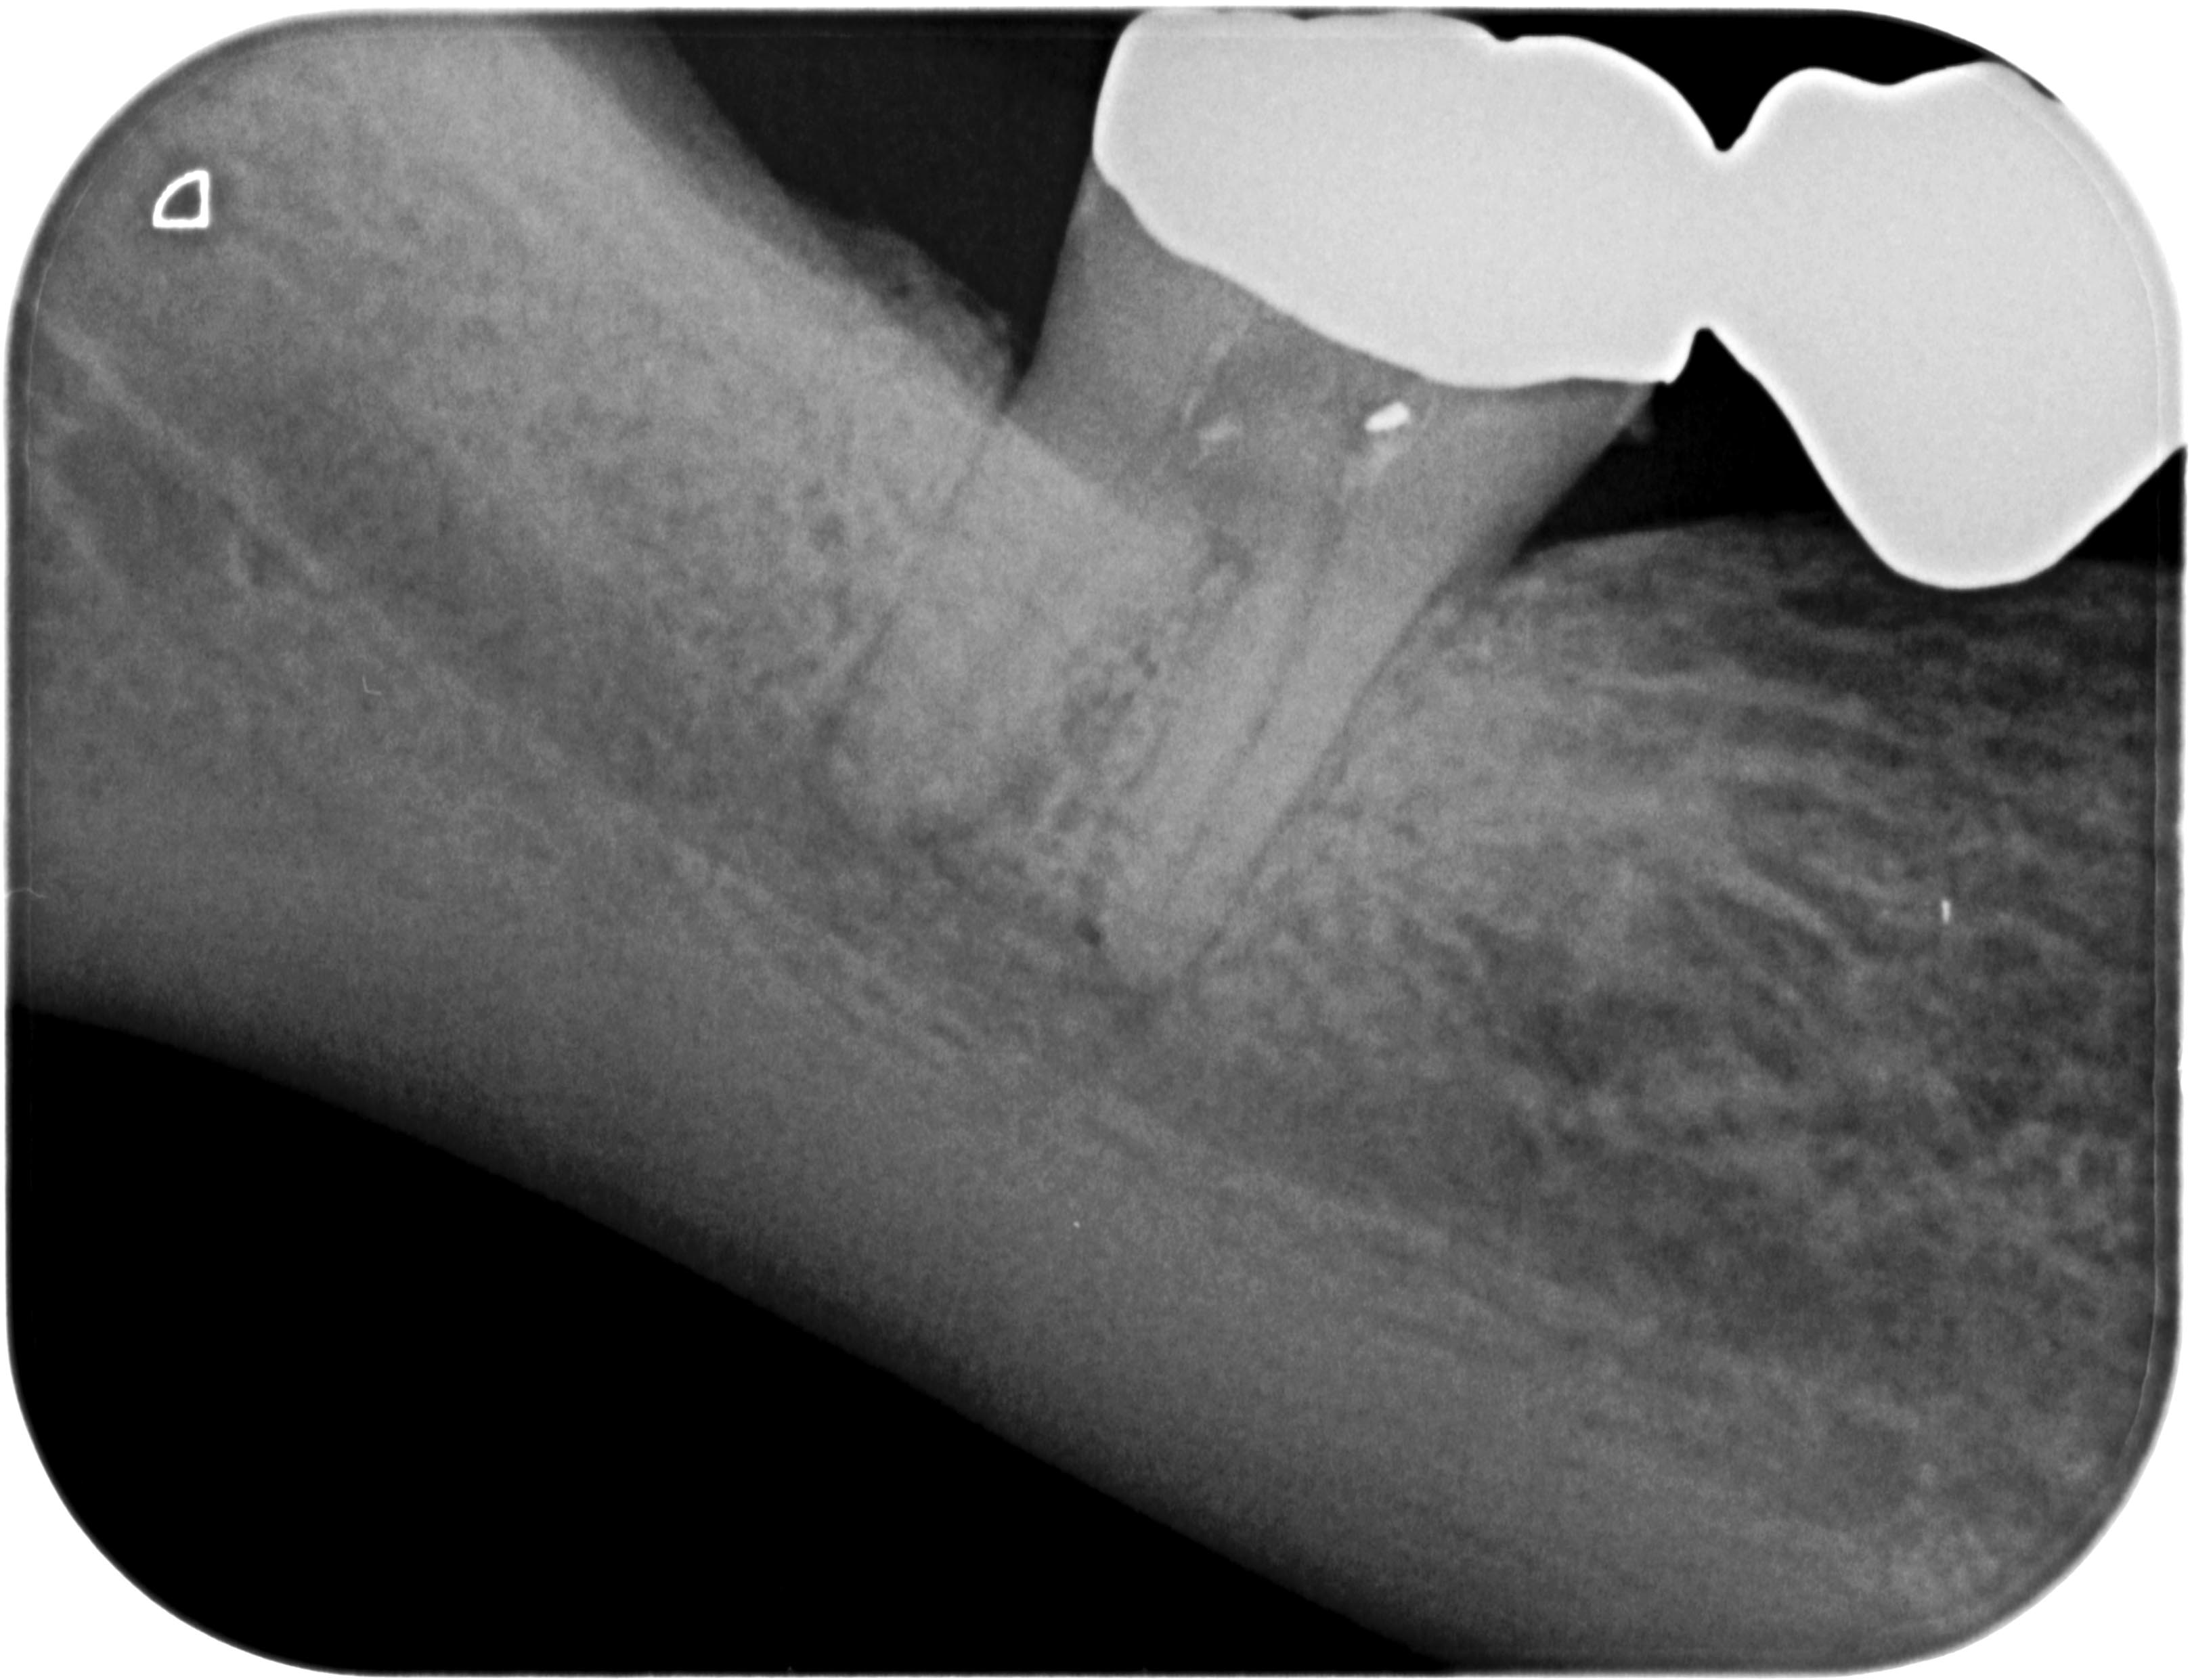

RÖ-1

Zahnschmerzen können grausam sein